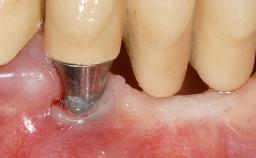

A 30-year-old woman was referred by her general dentist for evaluation of an esthetic complication related to previous implant treatment for congenitally missing maxillary lateral incisors. The patient’s chief complaint was the inadequate esthetic appearance of her smile. The case demonstrates the use of a combined approach to achieve optimal results. Two different flap designs - a tunnel technique and a coronally advanced flap - are employed based on the surgical objectives for the affected site.

Soft Tissue Grafting Yes

Soft Tissue Anatomy Intact Defective